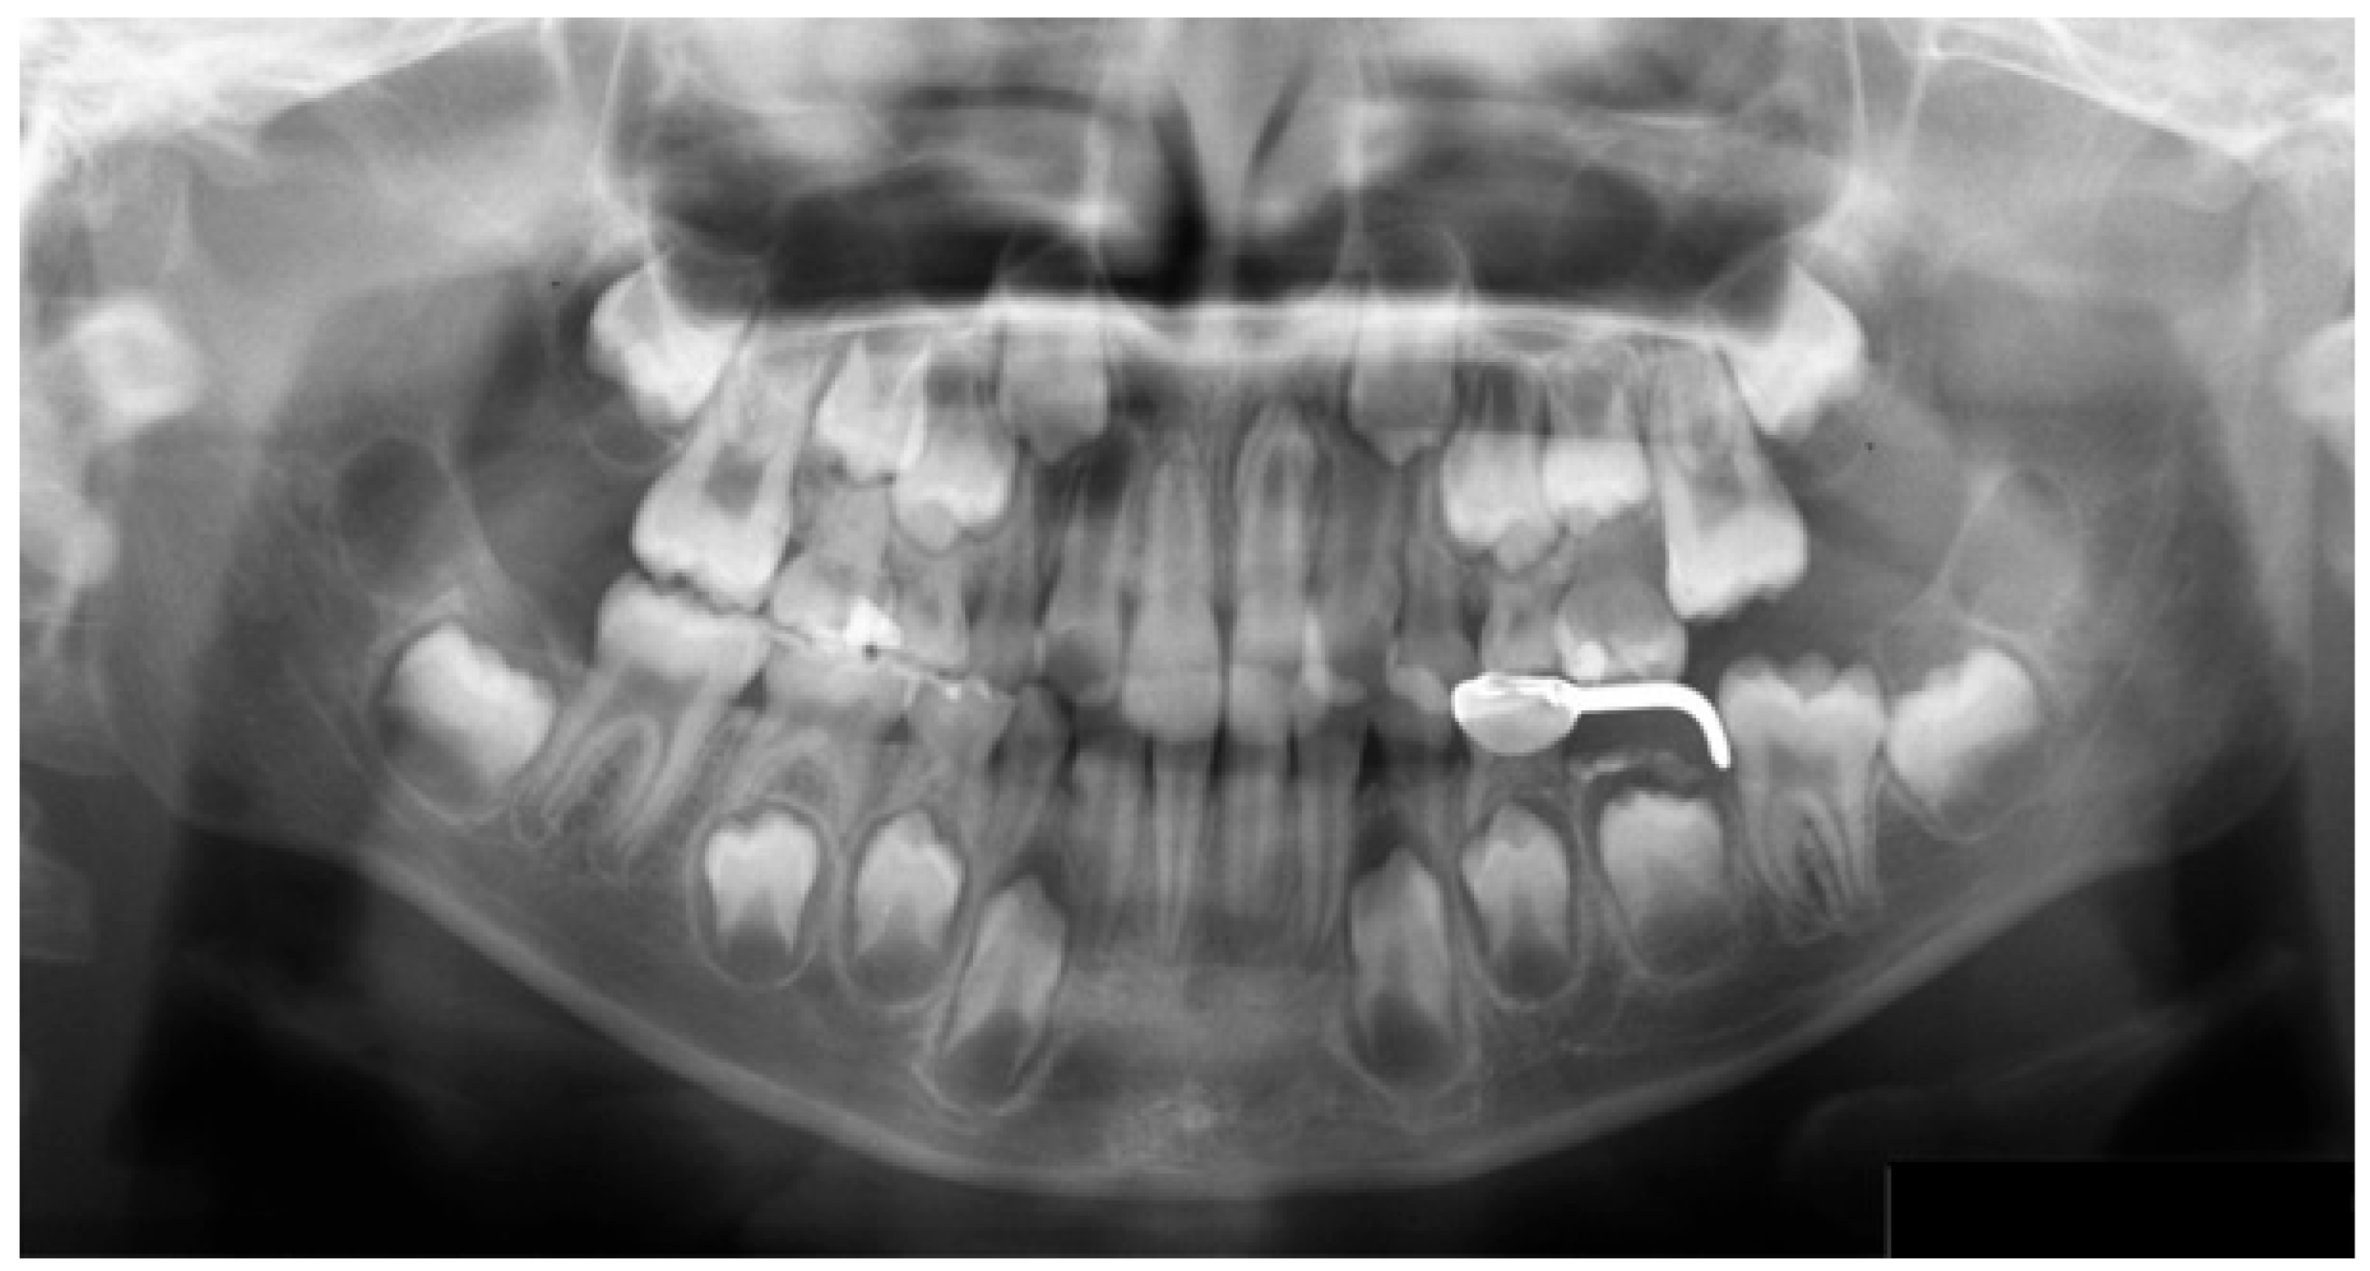

The eye movement patterns were classified into four groups: clockwise (R; n = 16, 29.6%), counterclockwise (L; n = 24, 44.4%), scattered (S; n = 9, 16.7%), and clustered (C; n = 5, 9.3%). No significant sex differences were observed in the distribution of eye movement patterns (χ²(3) = 1.33, p = 0.72). Representative examples of each pattern are shown in Figure 2. High-performing participants in the R group exhibited clockwise scan paths more frequently (Figure 2a), which were characterized by fixations distributed across the entire radiograph and relatively few saccades. An example of the L group is shown in Figure 2b, whereas the S group demonstrated a pattern dominated by saccades with very few fixations (Figure 2c). In the C group, fixation was restricted to specific landmarks (Figure 2d). This indicates a significant association between the categorical variables.

Figure 2. (a) R Group. (b) L Group. (c) S Group. (d) C Group.